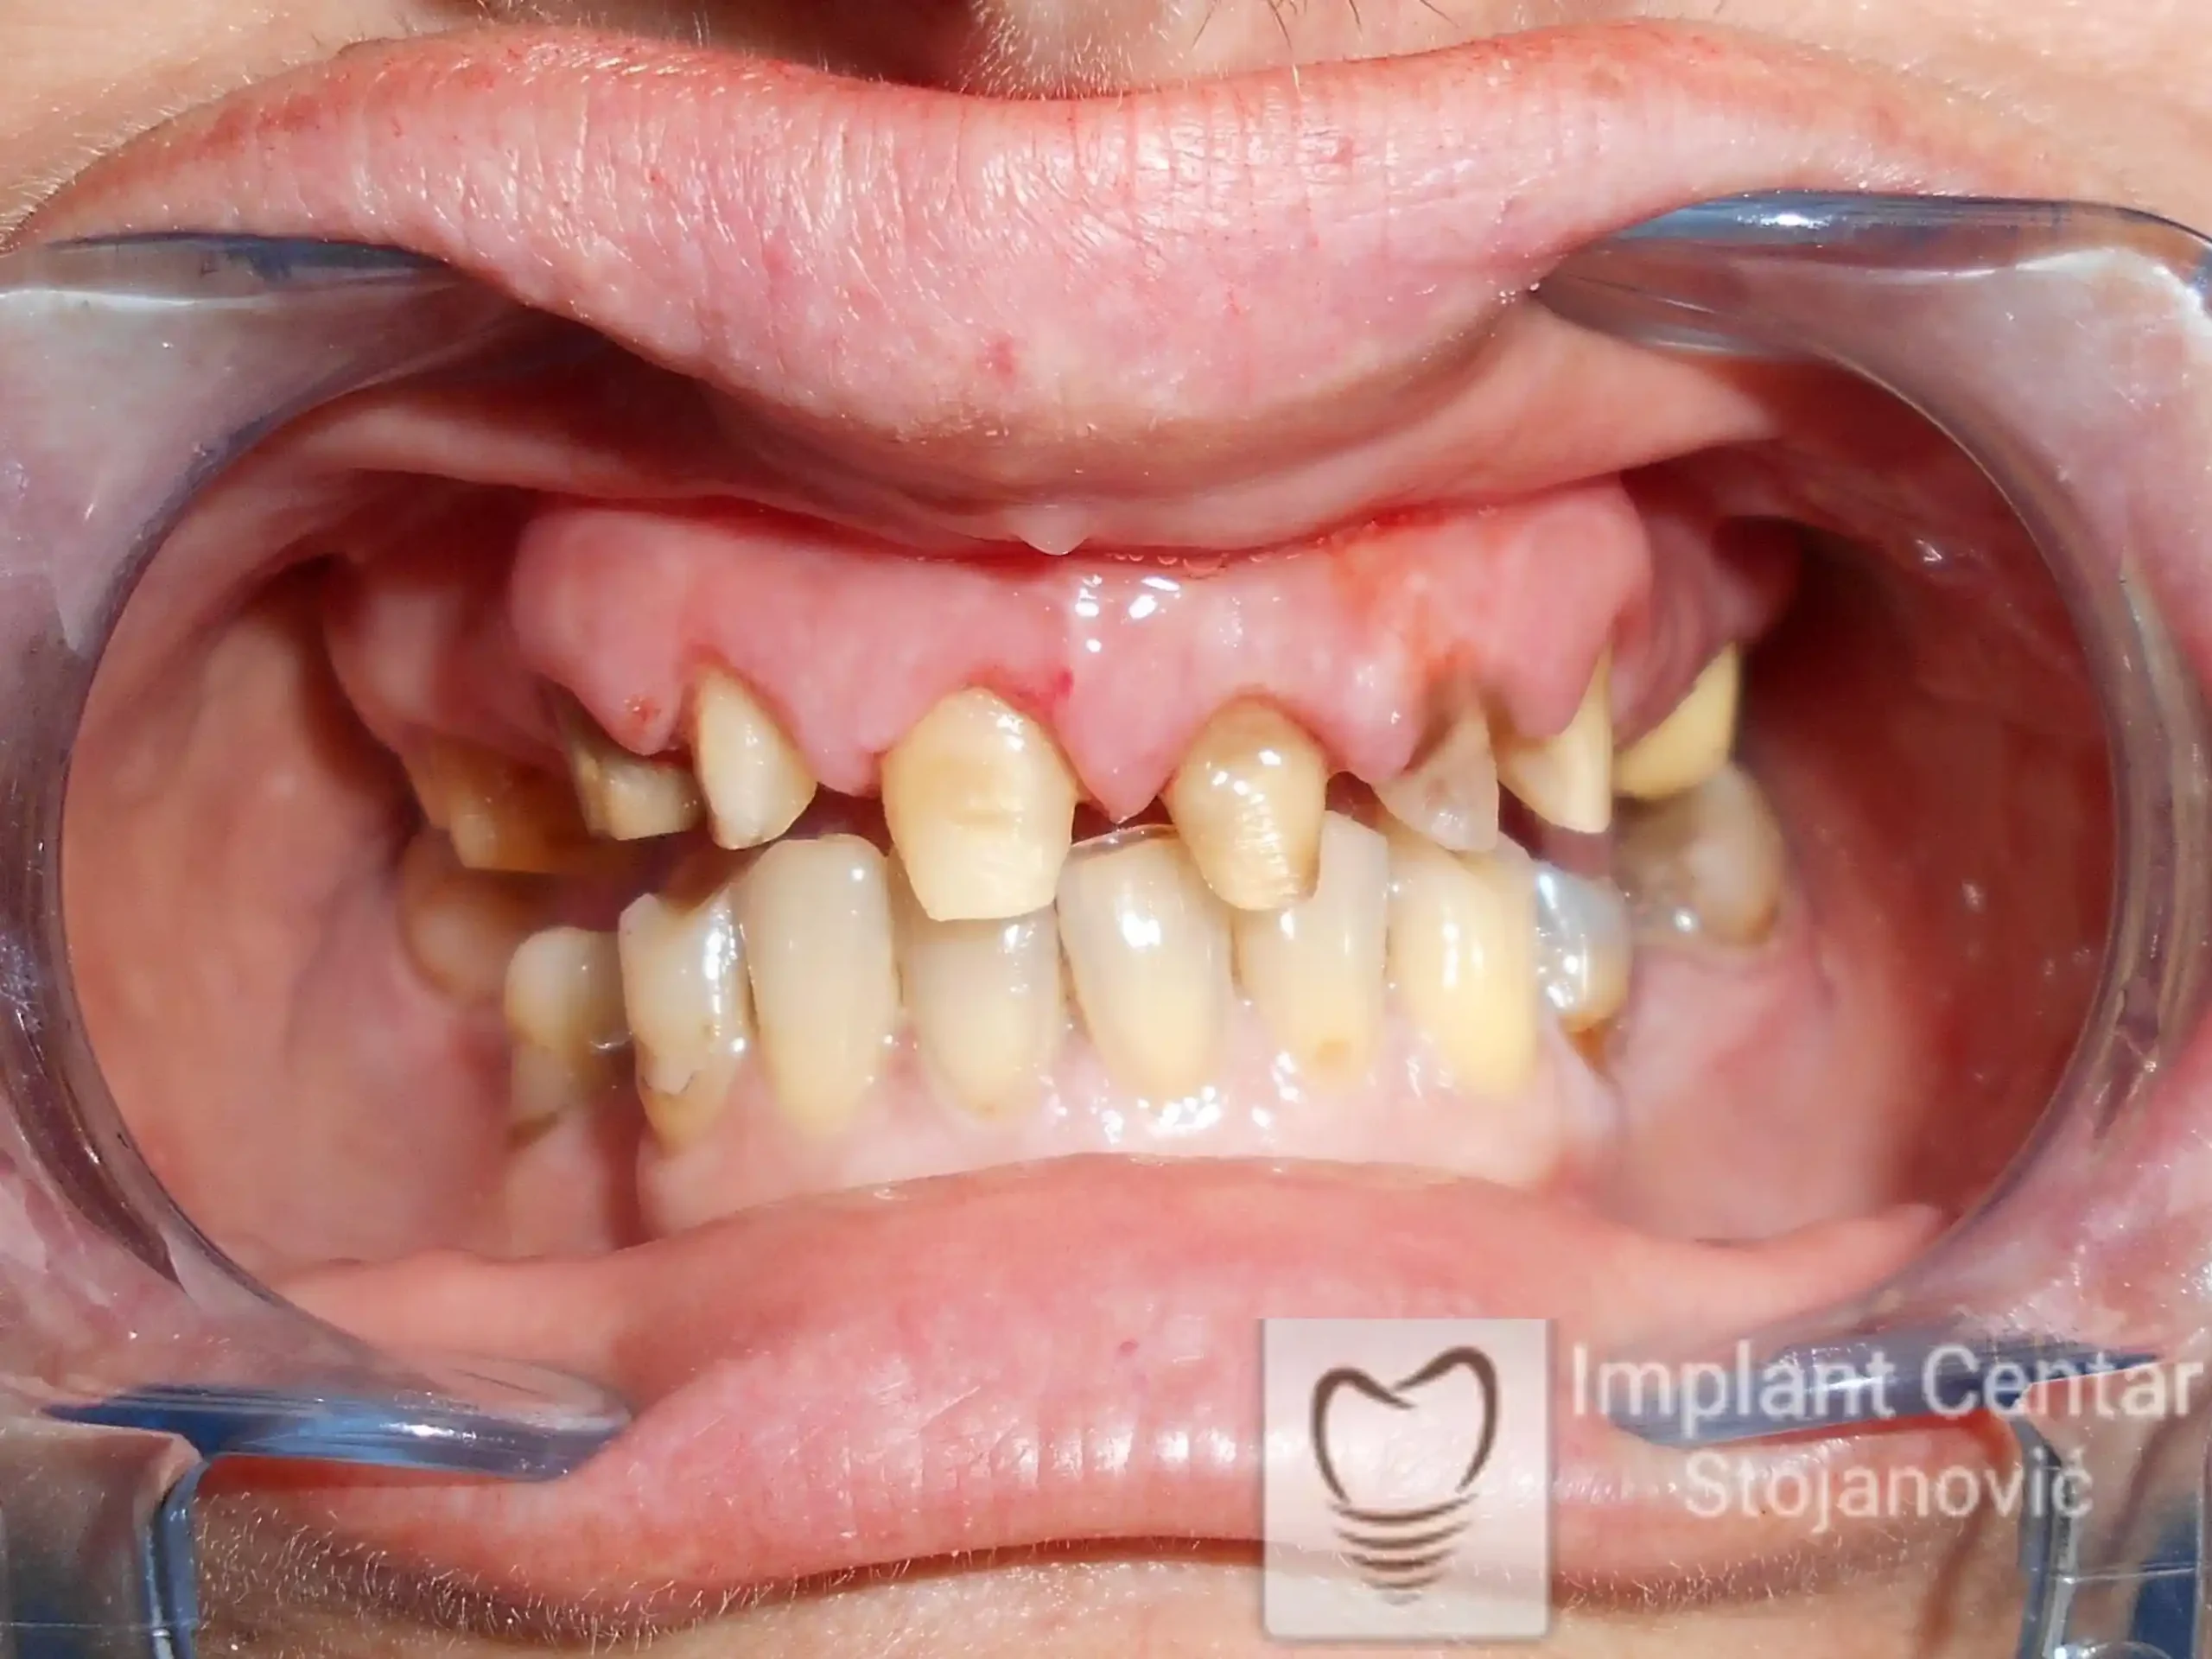

Pacijent sa rascepom usne, nepca i alveolarnog grebena uspešno je rehabilitovan fiksnim protetskim radom na implantatima. Pre dolaska u našu ordinaciju, pacijent je u gornjoj vilici nosio totalnu protezu preko preostalih zuba, dok je u donjoj vilici bio zbrinut parcijalnom mobilnom protezom. Tokom višegodišnje potrage za adekvatnim rešenjem, pacijent nije uspeo da pronađe zadovoljavajuću terapijsku opciju ni u zemlji ni u inostranstvu.

Nakon detaljnog kliničkog pregleda i analize radioloških snimaka, izrađen je sveobuhvatan plan terapije sa ciljem uklanjanja mobilnih proteza i postizanja maksimalne funkcionalne i estetske rehabilitacije. Zbog loše biološke vrednosti preostalih zuba, doneta je odluka o njihovom vađenju i ugradnji dentalnih implantata.